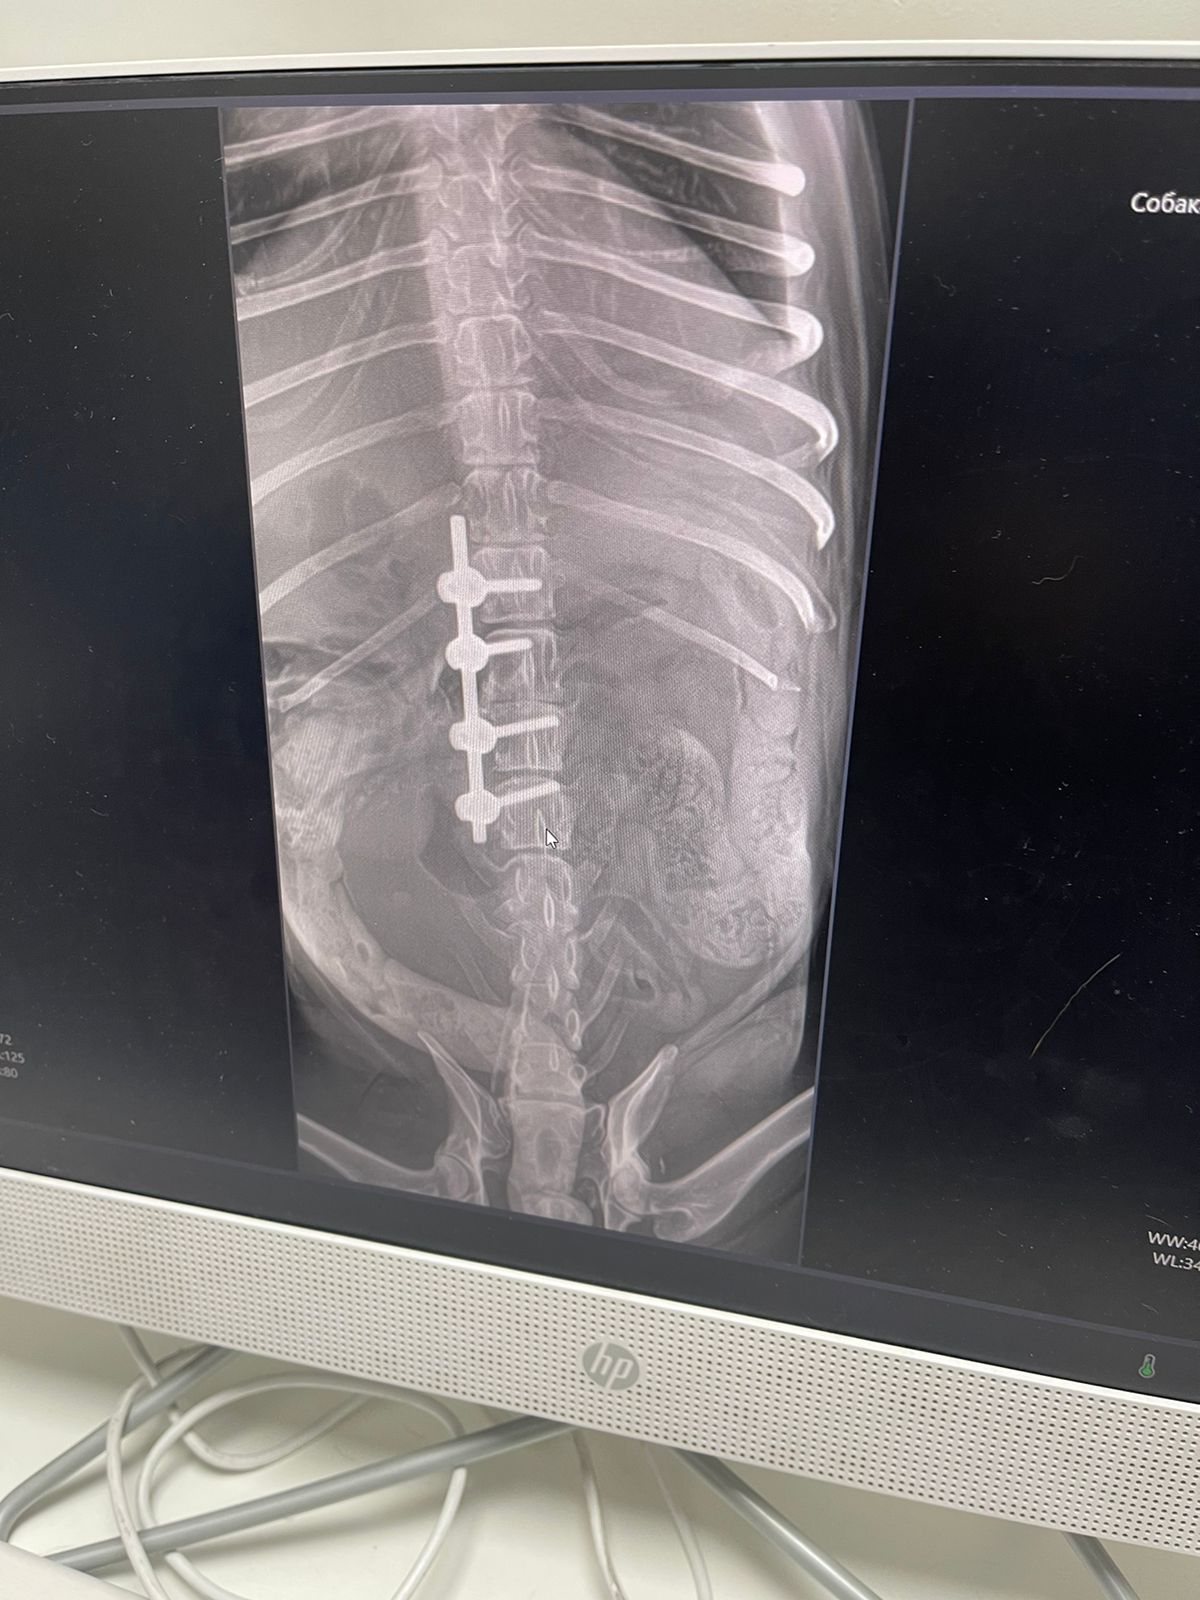

Марику сделали операцию. Один позвонок у него был развалившийся, второй что-то куда-то выдавливал. Но все не так плохо, мозг живой, чувствительность в лапах сохранилась на момент операции. Поставили стабилизатор позвоночника и что-то еще делали.

Чеки на сегодня. Скидку 15 процентов сделали.

Поговорила с врачом, сфоткала рентген с экрана компьютера.